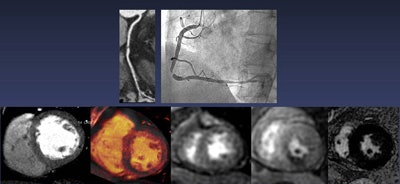

Combined dual-energy coronary CT angiography and CT myocardial perfusion imaging (CCTA-MPI) improves both the identification and discrimination of ischemia-causing coronary artery stenoses over CCTA alone, according to a Korean study presented at last week's RSNA meeting.

Compared with combined invasive coronary angiography/cardiac MR-MPI, CCTA with stress dual-energy CT (DECT) and MPI improves the predictive value of ischemia-causing coronary artery stenoses versus CCTA, but it only mildly improves the diagnostic performance of stress DECT-MPI alone, concluded Dr. Sung Min Ko, from Konkuk University Hospital in Seoul, South Korea, and colleagues.

The current study aimed to determine the diagnostic performance of stress DECT-MPI for identifying and excluding coronary artery stenoses that cause ischemia. The researchers prospectively examined 192 consecutive patients who underwent CCTA, DECT-MPI, invasive coronary angiography, and cardiac MR with MPI (CMR-MPI).

They used both DECT-MPI and CMR-MPI to look for the presence or absence of myocardial perfusion defects, while CCTA and invasive coronary angiography images were examined for the presence or absence of anatomically obstructive stenosis, defined as a stenosis greater than 50%.

Using electrocardiogram gating, the study team scanned the patients with a dual-source scanner (Siemens Healthcare) at 60% to 75% of the RR interval (140 kV and 100 mAs for the A tube; 80 kV and 165 mAs for the B tube). Scans began four minutes after adenosine infusion and followed injection of iodinated contrast using bolus tracking, Ko said.

"DECT is a novel method that allows for mapping of myocardial contrast for evaluation of myocardial perfusion," the authors wrote in their study abstract. "Stress DECT-MPI provides clinical benefit to patients with insufficiently evaluated coronary lesions by CCTA alone."